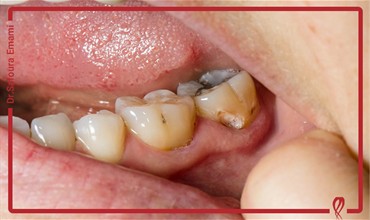

دکتر صفورا امامی متخصص درمان ریشه و عصب کشی

من صفورا امامی، متولد سال ١٣٥٩، متخصص درمان ریشه دندان و دارای رتبه دوم بورد تخصصی اندودانتيكس (درمان ریشه) در بین کلیه دانشكده هاي دندانپزشكی كشور در سال 1396 و در همان سال با عضویت در هـيأت علمی دانشگاه آزاد تهران مشغول به فعاليت شده و هم‎زمان مطب تخصصی خود را افتتاح كردم.